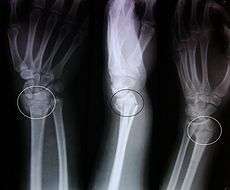

An X-ray image of a fractured radius showing the characteristic Colles' fracture with displacement and angulation of the distal end of the radius | |

A Colles' fracture is a fracture of the distal radius in the forearm with dorsal (posterior) and radial displacement of the wrist and hand.[1] The fracture is sometimes referred to as a "dinner fork" or "bayonet" deformity due to the shape of the resultant forearm. Colles' fractures are often seen in people with osteoporosis.